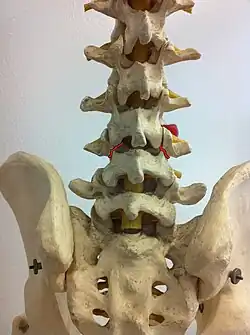

Pars interarticularis marked with red lines

Spondylolysis is a bony defect or fracture within the pars interarticularis of the vertebral arch in the spinal column. The vast majority of spondylolysis occur in the lumbar vertebrae, however it can also be seen in cervical vertebrae.[3] The lumbar vertebra consist of a body, pedicle, lamina, pars interarticularis, transverse process, spinous process and superior and inferior articular facets, which form joints that link the vertebrae together. When examining the vertebra, the pars interarticularis is the bony segment between the superior and inferior articular facet joints located anterior to the lamina and posterior to the pedicle. Separation of the pars interarticularis occurs when spondylolysis is present in the spinal column.[14]